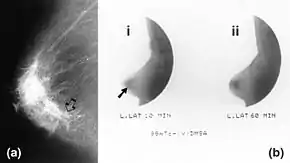

Mammography (left) and DMSA scintimammography (right) images of 4.5cm breast carcinoma | |

99mTc-DMSA and 99mTc-MDP may also been used, but provide less sensitive results.[7]